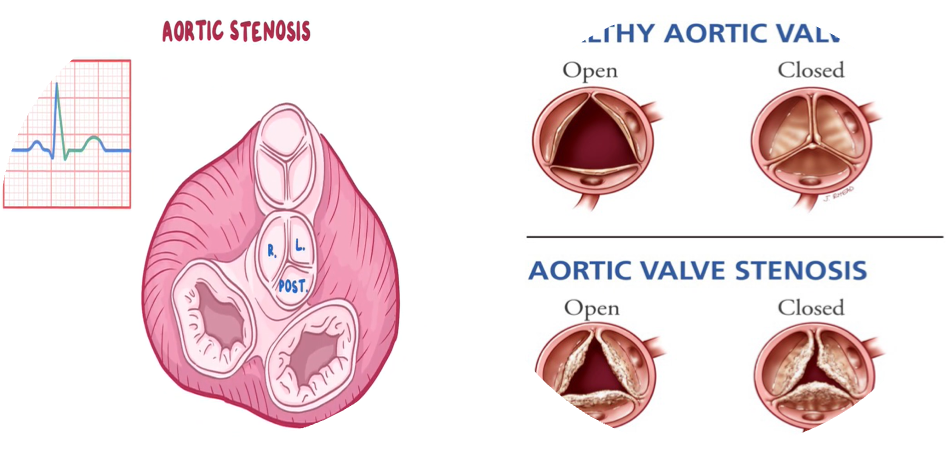

Normal Aortic Valve

Three cusps, crescent-shaped

- 3 commissures

- 3 sinuses

- Supported by fibrous annulus

- 3.0 to 4.0 cm2

Pathophysiology

Progressive narrowing: ↓ flow across the valve. ↑ LV pressure, LV hypertrophy (Stroke volume), and ↑ end-diastolic pressures and non-compliant LV.

Narrowed opening area of the aortic valve during systole → obstruction of blood flow from the left ventricle (LV) → increased LV pressure → left ventricular concentric hypertrophy, which leads to: Increased LV oxygen demand. Impaired ventricular filling during diastole → left heart failure. Reduced coronary flow reserve. Initially, cardiac output (CO) can be maintained. Later, the decreased distensibility of the left ventricle reduces cardiac output and may then cause backflow into the pulmonary veins and capillaries → higher afterload (pulmonic pressure) on the right heart → right heart failure.